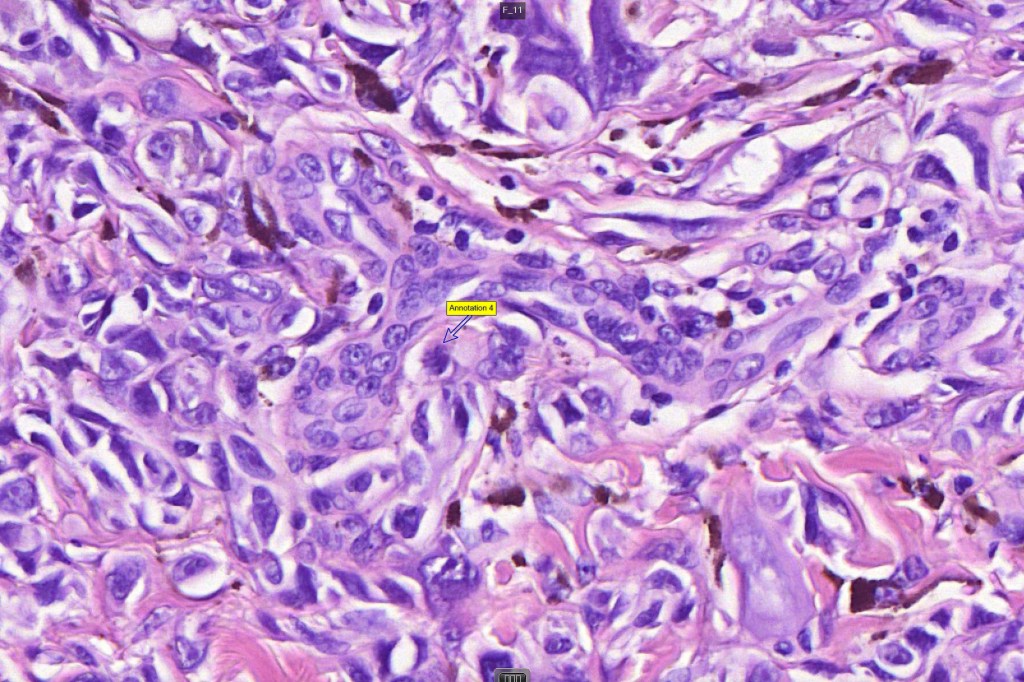

•Junctional nests often vertically orientated, dyscohesive with a surrounding retraction artifact

•Pleomorphism is almost invariable but affects all of the population to the same extent i.e., the cells & nuclei all look very much the same

•Spindle cell nests often display a “raining down” growth pattern

•Spindle cells have abundant cytoplasm and vesicular nuclei with small nucleoli

•Epithelioid cell variants often show greater pleomorphism and cells can frequently appear bizarre with abundant, sometimes ground glass cytoplasm and large vesicular nuclei with prominent eosinophilic nucleoli, multinucleate cells are often seen

•Intracytoplasmic pseudoinclusions commonly present in epithelioid cells

•Kamino bodies (often multiple) are a characteristic feature